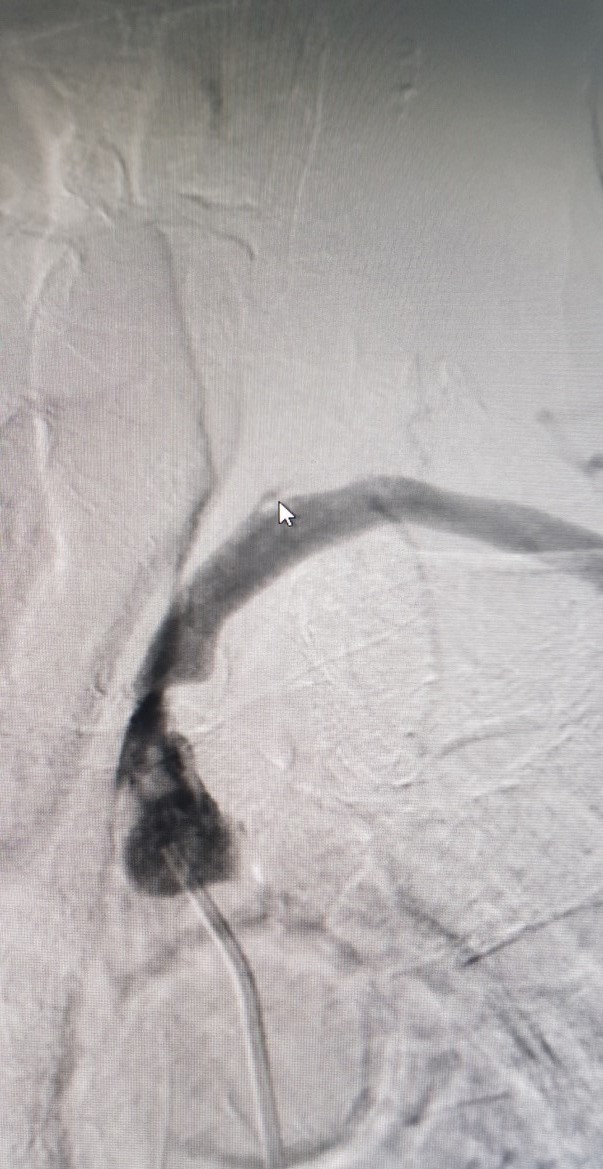

Sau can thiệp

Hình ảnh can thiệp động mạch dưới đòn tại Bệnh viện Đa khoa Tỉnh Quảng Trị